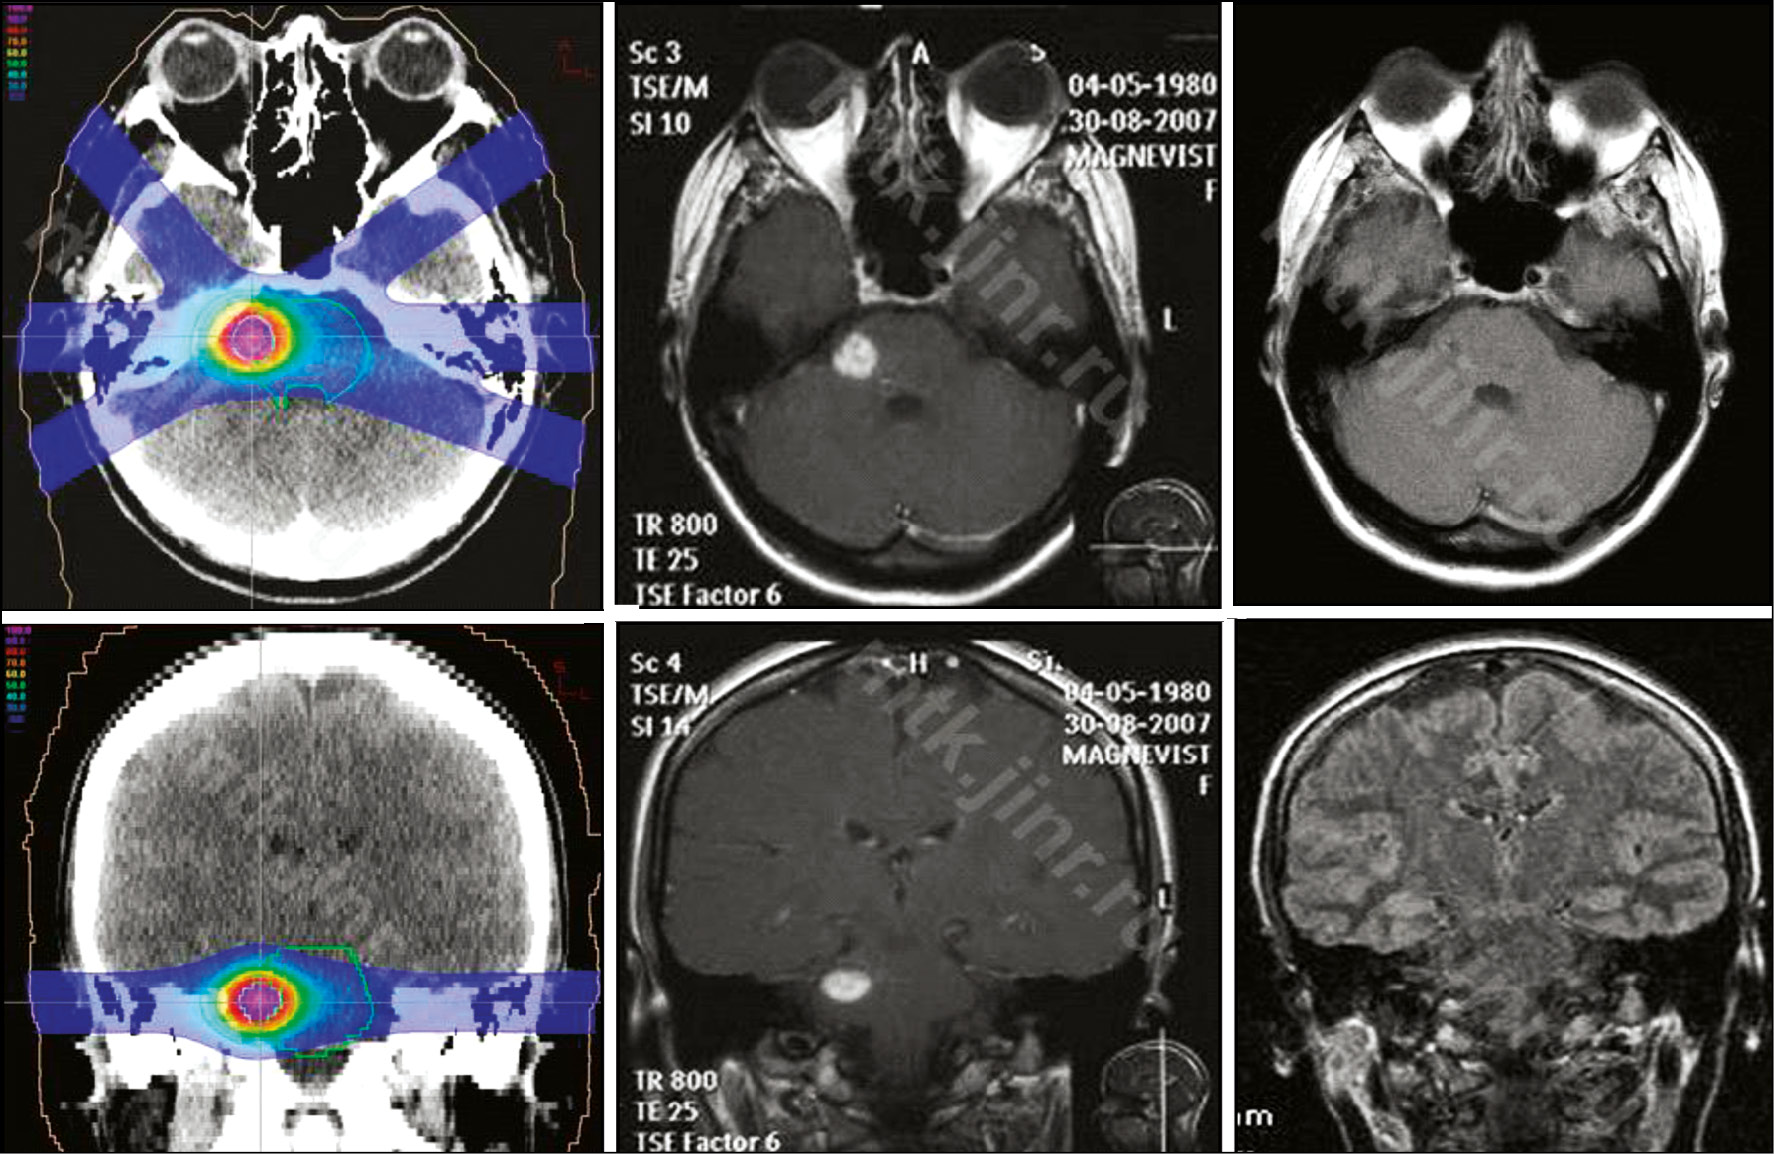

The treatment effect is observed within 5–90 months after application. Complete obliteration of the neoplasm is achieved in 70% of cases. The plan of proton radiosurgery of the cavernoma in the peristem is presented in Fig. 1 [47].

Fig. Plan of proton radiosurgery of the periostemal cavernoma: MRI with contrast before treatment and after 3 months (complete resorption of the cavernoma).